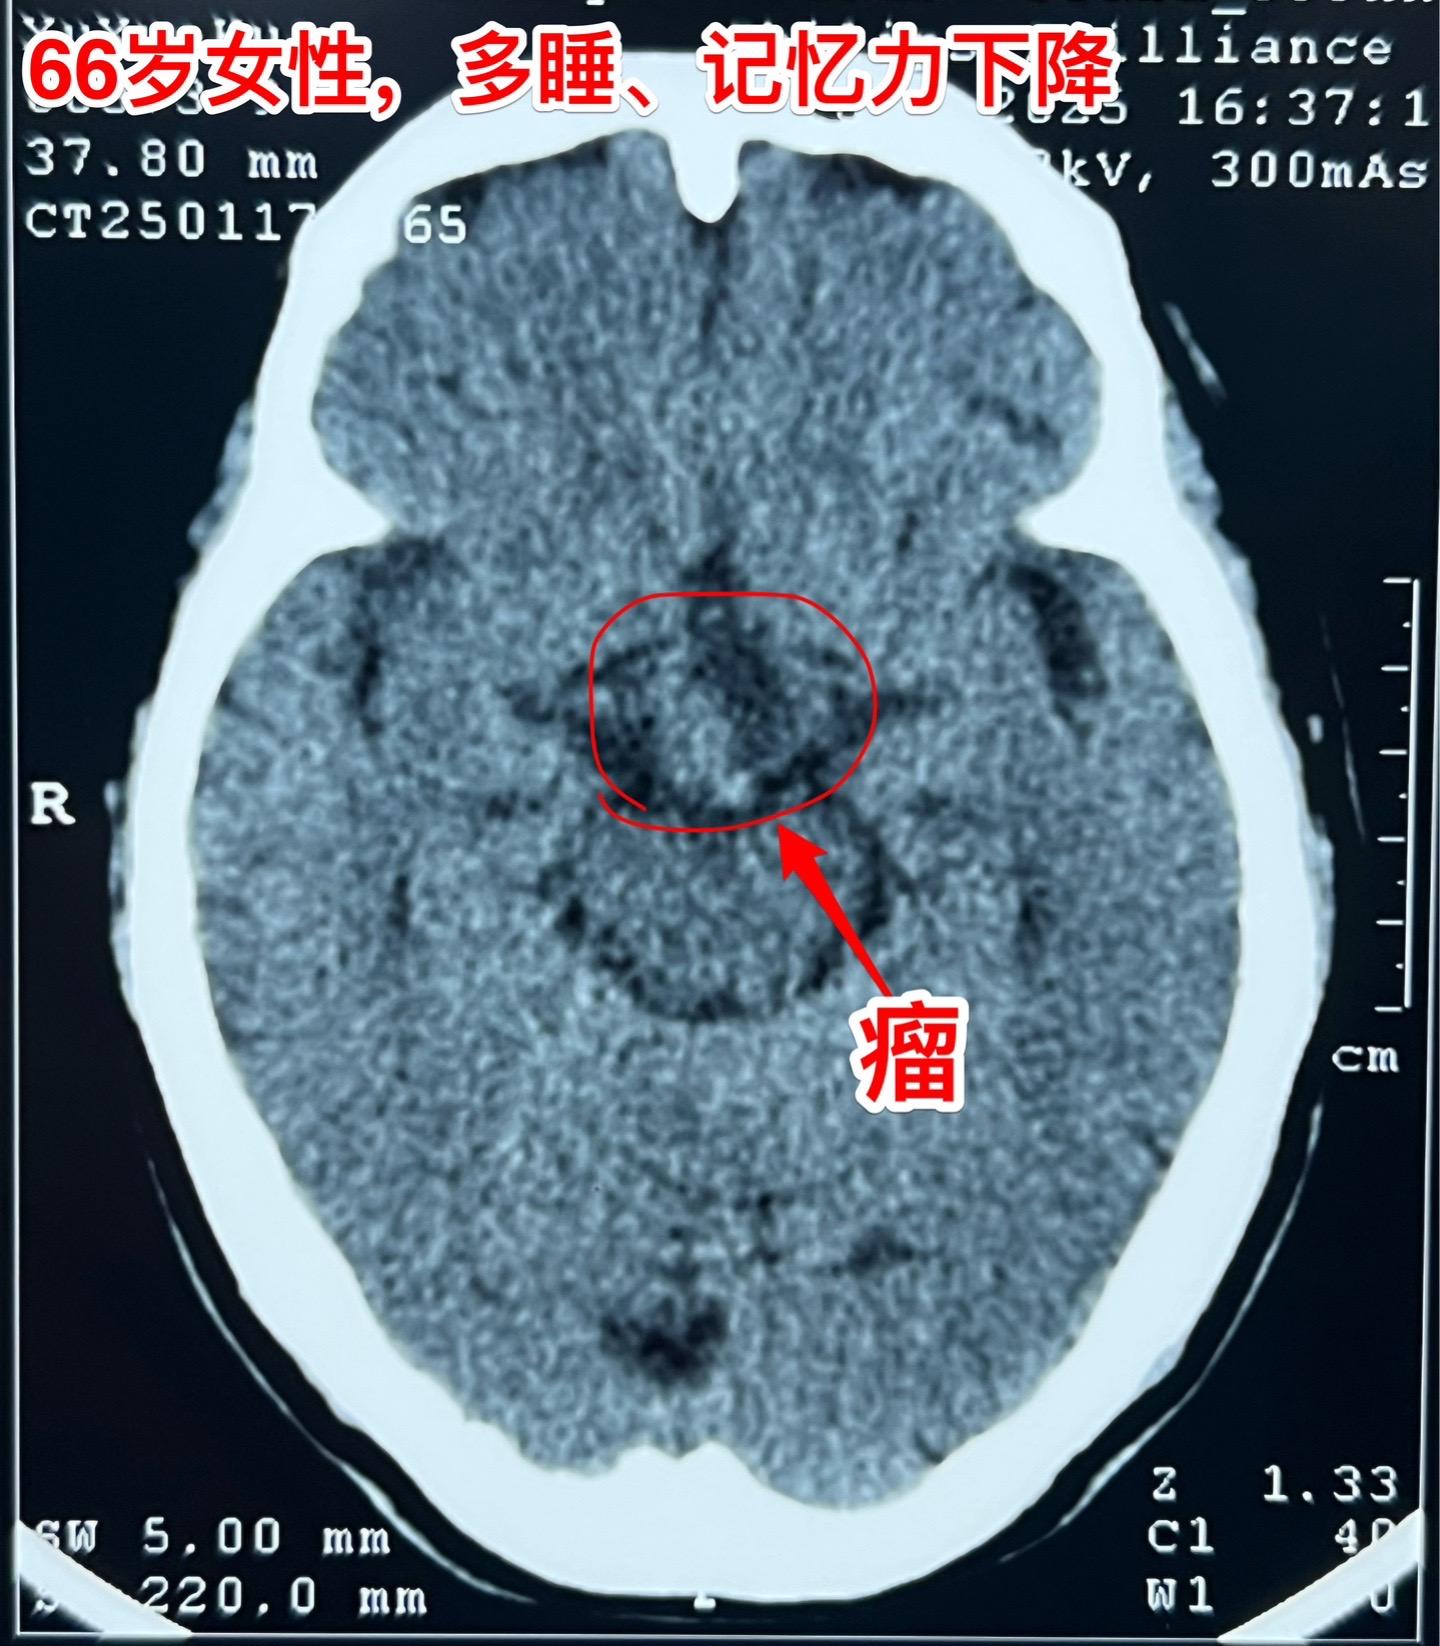

是颅咽管瘤吗?鞍区肿瘤的定性诊断是很难的。66岁女性,泰州人。因为多睡、记忆力下降在外院检查脑部发现脑部肿瘤。病人的多睡症状越来越严重。肿瘤位于鞍上区域,而且伴有脑积水。外院怀疑是颅咽管瘤?或者是别的肿瘤? 病人曾经在上海就医过,因担心手术风险,通过三博脑科医院院长找我咨询,随后决定到我院作手术。 1月24日作了开颅手术(这是我科春节前的最后一个择期手术),手术中发现肿瘤的性状不符合乳头型颅咽管瘤,分两次取标本送快速冰冻病理检查,报告考虑是胶质瘤。 下丘脑胶质